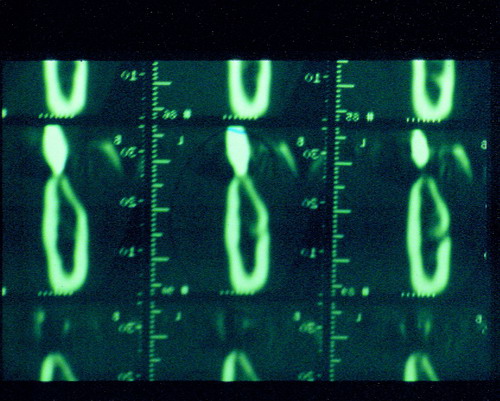

LA OCLUSIÓN MUTUAMENTE PROTEGIDA ES UN VIEJO CONCEPTO QUE CONSISTE EN LA MUTUA INTERACCIÓN DE LOS DISTINTOS GRUPOS DENTARIOS ENTRE SI. DE ESTA FORMA, LA TABLA PREMOLAR / MOLAR DE AMBOS HEMIMAXILARES ANTAGONISTAS, DETIENEN EL CIERRE MANDIBULAR EN CÉNTRICA, LOS CANINOS DISCLUYEN LAS PIEZAS POSTERIORES DURANTE LAS TRANSTRUSIONES, Y EL GRUPO INCISIVO LO MISMO DURANTE LAS PROPULSIVAS. SIN EMBARGO, DICHO CONCEPTO ES LIMITADO A LAS PIEZAS DENTARIAS, SIN TENER EN CONSIDERACIÓN LA IMPORTANTE FUNCIÓN QUE RECAE SOBRE LA ATM Y EN EL SOPORTE DE PRESIONES DURANTE ESTA DINÁMICA. ES ASI QUE EN EL AÑO 1981, EL DR. ANIBAL ALONSO GENERA EN LA CIUDAD DE BUENOS AIRES UN CONCEPTO MAS AMPLIO QUE DENOMINÓ : OCLUSION MUTUAMENTE COMPARTIDA. REF I EN EL QUE AMPLÍA EL CONCEPTO ANTERIOR, HACIENDO PARTÍCIPE A LA ATM EN LA MISMA. CUANDO EXISTE CARENCIA DE PIEZAS DENTARIAS POSTERIORES, YA SEA DE UN SOLO LADO O DE AMBOS , EL CIERRE MANDIBULAR ES DETENIDO POR LAS PIEZAS RESTANTE, FORZANDO A LA ATM A SOPORTAR PRESIONES MUY SUPERIORES A AQUELLAS PARA LAS QUE ESTA PREPARADA. FIG1 FIG2 FIG3 LUEGO DEL ESTUDIO CLÍNICO DE RIGOR, DONDE SE EVALÚA RADIOGRÁFICA Y PERIODONTALMENTE, SE PROCEDE A TOMAR MODELOS DE ESTUDIO Y MONTAR EN ARTICULADOR SEMIAJUSTABLE, SOBRE EL CUAL SE REALIZA UN ENCERADO PROGRESIVO DE DIAGNÓSTICO, A PARTIR DEL CUAL SE CONFECCIONA UN JUEGO COMPLETO DE PROVISIONALES DE AMBAS ARCADAS , INCLUYENDO LAS PIEZAS FALTANTES. SE ABORDA EL CASO YA QUIRÚRGICAMENTE DONDE EN UNA PRIMERA ETAPA SE TALLAN PRIMARIAMENTE LAS PIEZAS DENTARIAS Y SE PROCEDE, EXODONCIANDO EL INCISIVO CENTRAL SUPERIOR DERECHO, A REALIZAR UNA ROG(REGENERACIÓN ÓSEA GUIADA), PARA INMEDIATAMENTE INSTALAR PARTE DE NUESTROS PROVISORIOS EN LA GUIA ANTERIOR. SE ADAPTAN A LOS SECTORES POSTERIORES LAS PRÓTESIS REMOVIBLES QUE PORTABA, Y SE ESPERAN CUATRO MESES, AL CABO DE LOS CUALES SE REALIZA UN ESTUDIO CON DENTASCAN, MEDIANTE EL USO DE UNA FÉRULA RADIOLÓGICA CON TUBOS METÁLICOS , QUE NOS SERVIRÁ TAMBIÉN DE GUÍA QUIRÚRGICA. PROCEDEMOS ENTONCES A LA IMPLANTACIÓN DE LOS SECTORES EDÉNTULOS MEDIANTE IMPLANTES ROSCADOS Y TÉCNICA SEMI SUMERGIDA. TRANSCURRIDAS OCHO SEMANAS OBSERVAMOS UNA CORRECTA SALUD PERIMPLANTARIA, Y REALIZAMOS LA INSTALACIÓN DE LOS ABUTTMENTS ALCANZAMOS ENTONCES EL PUNTO EXACTO DONDE DEBEREMOS COMENZAR A RECONTRUIR EN FORMA PERMANENTE. PAZ DEL SISTEMA: CENTRICIDADARTICULAR-PAZ MUSCULAR-ESTABILIDAD- -ACOPLAMIENTO. BASES FUNDAMENTALES DE LA OCLUSIÓN ORGÁNICA FIG41 FIG42 PROCEDEMOS NUEVAMENTE A TOMAR IMPRESIONES, EN ESTE CASO DEFINITIVAS , MONTAR NUEVAMENTE EN ARTICULADOR, Y CONSTRUIR LAS RESTAURACIONES PERIFÉRICAS TOTALES EN BASE A PORCELANA SOBRE ORO GALVANIZADO. REF. II SOBRE LAS MISMAS TERMINADAS Y YA EN BOCA, CHEQUEÁMOS TODOS LOS ELEMENTOS QUE CONSTITUYEN UNA REHABILITACIÓN ORAL INTEGRAL, DESDE LA SALUD ENDODONTICA DE PIEZAS TRATADAS O NO, LA SALUD PERIODONTAL, EL AJUSTE PERIFÉRICO DE LAS RESTAURACIONES, LA ESTABILIDAD EN LA ATM, Y LAS FUNCIONES OCLUSALES, CHEQUEOS ESTOS QUE SE REPETIRAN EN CADA UNO DE LOS CONTROLES POST OPERATORIOS. FIG46 FIG47 FIG48 FIG66 FIG67 REFERENCIAS: REF I: OCLUSIÓN Y DIAGNÓSTICO EN REHABILITACIÓN ORAL REF. II ELECTROFORMACIÓN EN ODONTOLOGÍA RESTAURADORA.